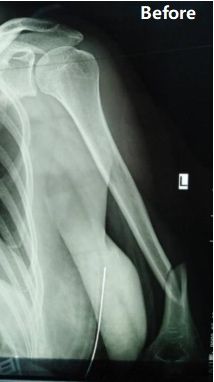

Caso compartido | Fractura del húmero diafisal del tercio medio a distal

Resumen del caso: Una paciente de 48 años de edad fue diagnosticada como Fractura del tercio medio a distal del eje humeral izquierdo (clasificación AO: tipo B1).